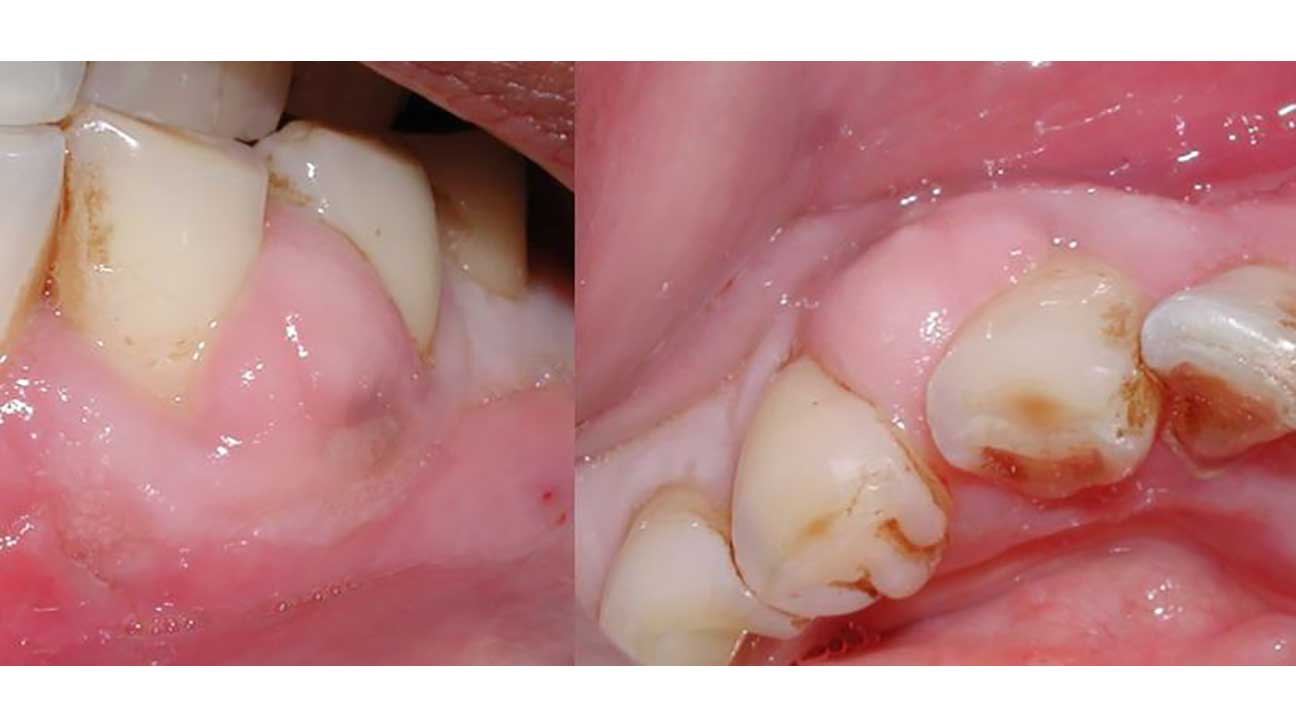

Tooth Abscess is commonly due to bacterial infection that grows in the tooth's pulp, bad tooth decay, gingivitis, gum infection, broken teeth, or a misshaped root canal procedure. These dental problems can lead to the loss of the tooth's enamel, leading to the bacteria penetrating the pulp. Infection may move from the root of the tooth to the jaws.

Symptoms are what somebody feels and tells about his or her health while symptoms are what details people, like a dentist or pericoronitis, may notice or detect. A gum abscess is diagnosed easily by the signs and symptoms told by the patient. If you are in doubt, meet the periodontist near me, and further diagnosis from conventional dental radiographs like X-rays. Typical signs and traits of a dental abscess are:

What is the reason behind the dental abscess:

The notable reason for contamination results from the development of germs in the tooth cavity affecting the tissues and bones of the neck. If you don’t take any step regarding the contaminated tooth and it is left untreated, tooth infection will frame and the disease may spread to the gums, jawbone, and different zones which can be serious. Any tooth can become an ulcer, yet the infected teeth are more inclined to create serious dental ailments due to the trouble to reach and clean them. More often than not, infected teeth are removed to keep away the inconveniences of dental soreness.

A dental abscess normally leads from the complexity of tooth decay or other reasons such as: